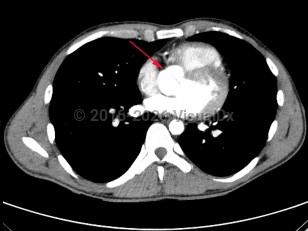

Cardiac tamponadeCardiac tamponade

Pulmonary embolismPulmonary embolism

PericarditisPericarditis